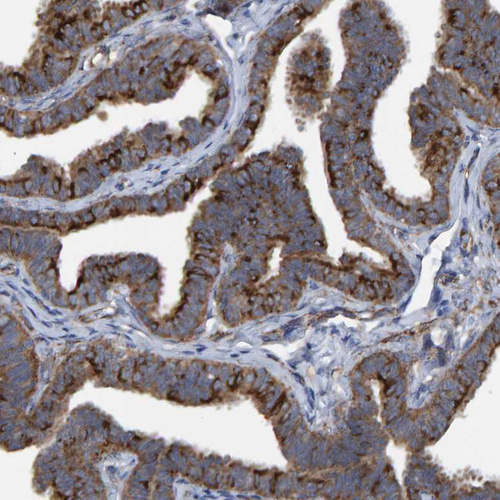

Immunohistochemical staining of human cerebral cortex shows strong positivity in neuropil.